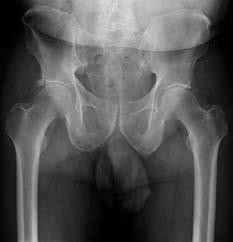

Question 2:

A 75-year-old woman sustains a displaced femoral neck fracture after a mechanical fall. Which of the following is the predominant blood supply to the femoral head that is at risk of disruption in this injury?

Correct Answer: Deep branch of the medial femoral circumflex artery

Explanation:

The predominant blood supply to the adult femoral head is provided by the lateral epiphyseal artery, which is the terminal branch of the medial femoral circumflex artery (MFCA). This runs along the posterosuperior aspect of the femoral neck and is frequently disrupted in displaced femoral neck fractures, leading to a high risk of avascular necrosis.